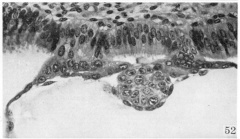

Contact area between the embryo and the endometrial cell culture

Contact area